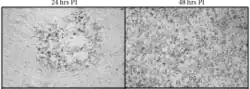

| B virus spread in murine cells with time at 24 and 48-hours post infection (PI) | |